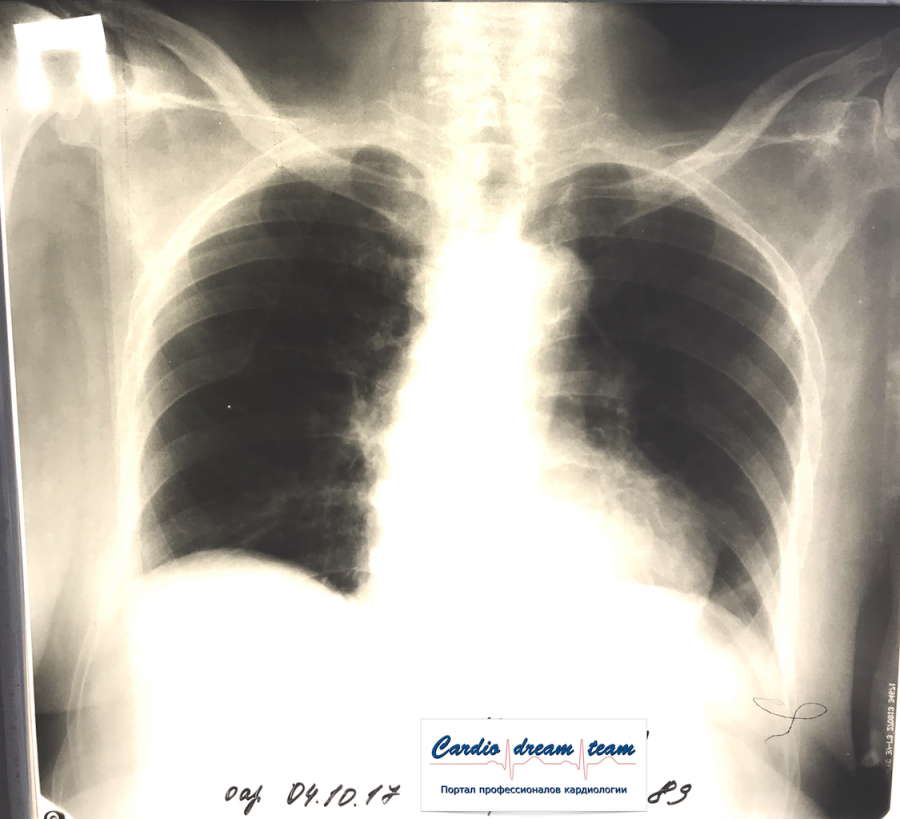

Двухсторонняя пневмония

Вложения:

IMG_0886.png

IMG_0886.png [ 759.15 KiB | Просмотров: 23128 ]

IMG_7045.png

IMG_7045.png [ 782.71 KiB | Просмотров: 23128 ]

IMG_7003.JPG

IMG_7003.JPG [ 121.75 KiB | Просмотров: 23128 ]